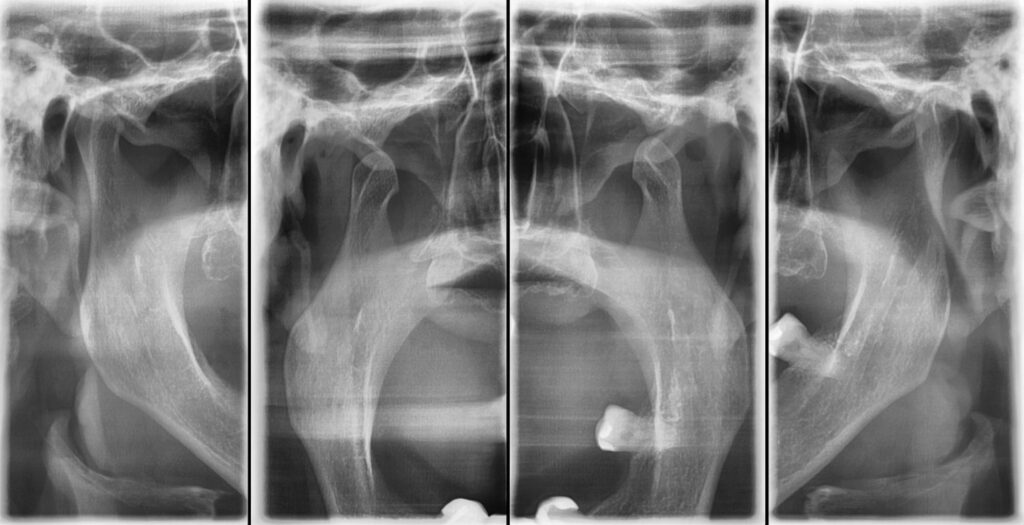

A radiografia da articulação temporomandibular (ATM) permite a avaliação detalhada dessa articulação crucial para a função mastigatória.

Imagem específica da ATM, sem interferência de outras estruturas.

Alta resolução para diagnóstico preciso.